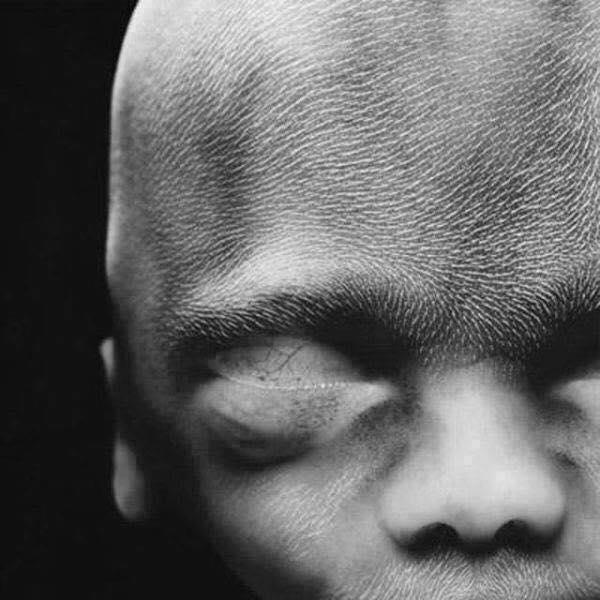

Semana 16, medindo por volta de 11,5 centímetros e pesando aproximadamente 100 gramas

O esqueleto consiste basicamente em cartilagem e o sistema circulatório é visível através da pele translúcida